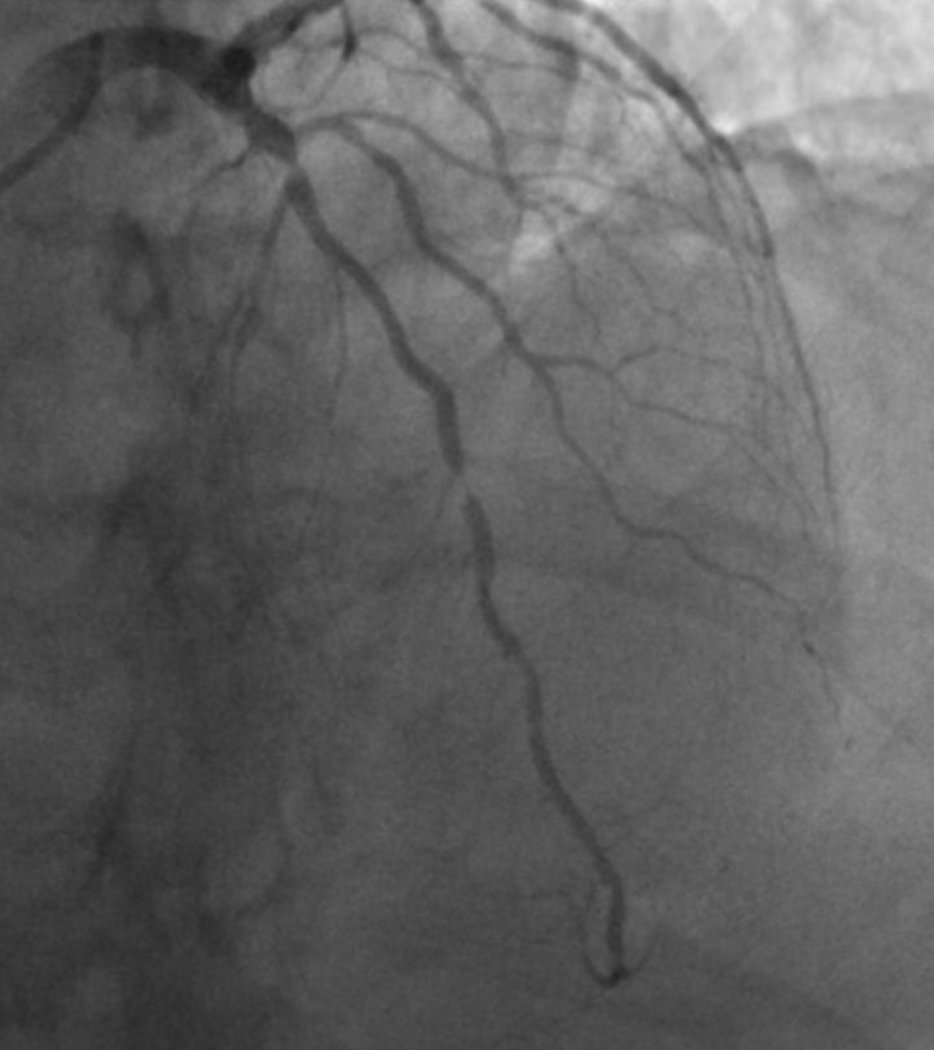

Almost 60 years later and all emergency roads lead from Troon to either Ayr or University Hospital Crosshouse, a couple of miles outside Kilmarnock, which opened in 1984 and in 2023, unfortunately, was brought to literary infamy by John Niven’s best-selling memoir O Brother. It dealt with the tragic death by suicide there of his brother Gary, from Irvine. I know, however, because my daughter has worked there and loved it, that Crosshouse is the place for me, suffering as I am from chest pain and all the panicky fears associated with a decade of living with a much-repaired and genetically dodgy heart. Ten years ago, it was a close thing. That Lateral Anterior Descending Artery had narrowed in several places to almost nothing. Like trying to squeeze the entire Clyde estuary through the Forth and Clyde Canal.

It’s a tribute to the Cath Lab (catheterisation laboratory) at Aberdeen Royal Infirmary (especially the bravery and skill of Dr Ryan), the Gilbert Bain Hospital in Lerwick, various GPs and other doctors, notably ones named Morton and Bowie that I’m still functioning today. Many nurses, paramedics, ambulance drivers, Scottish Air Ambulance pilots and porters, too. The full and glorious of panoply of care in Scotland’s NHS. Heartfelt thanks, always. Through technology and magic, arteries have been expanded by balloons and braced with mesh. Add a daily cocktail of medications and blood will flow. Has been flowing.